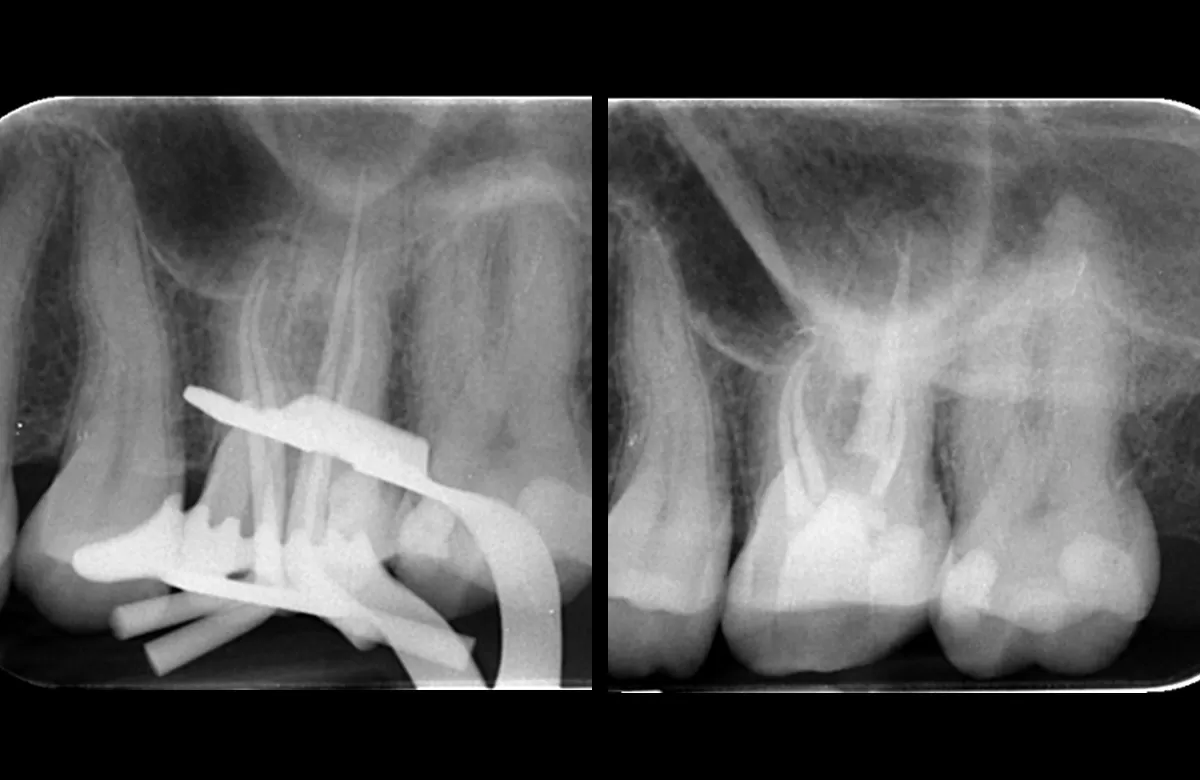

Pre obturation periapical radiograph of the tooth 16, checking cone length